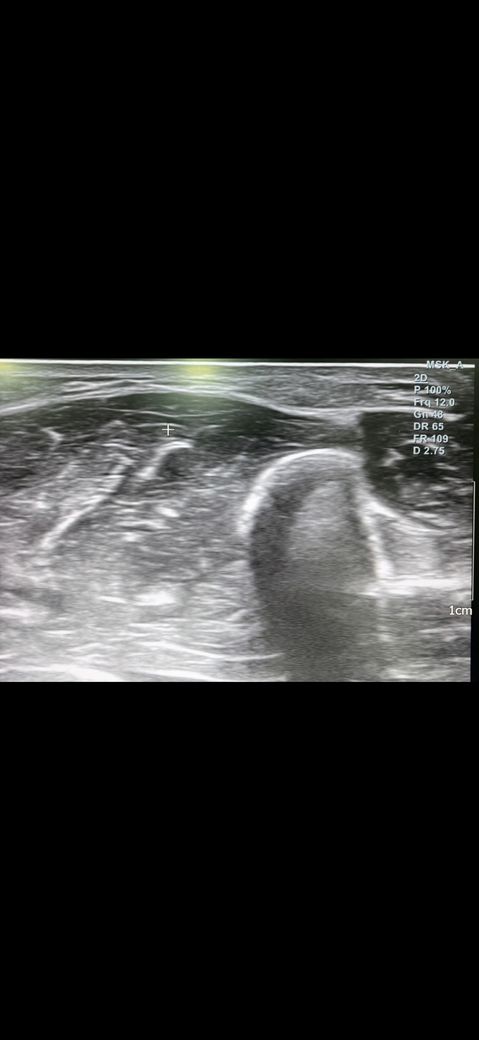

예전에 병원에서 팔에 동글동글하게 두 군데 정도 뭐가 만져지길래 초음파 사진을 찍고왔습니다.

해당 병원에서는 지방종같다고 하셨는데 생긴지 3년은 지난 것 같은데 계속 신경쓰이고 걱정이 되는데 사진의 종양이 지방종이 맞을까요?

• 3번 째 사진

초음파의 경우 정확한 진단보다는 양성 내지 악성 양상을 보는 검사 중 하나라고 생각해 주시면 좋고, 보통은 지방종의 경우 균질하고 경계가 명확한 모양을 띠고 있어, 질문자님의 사진상으로 볼 때에는 지방종일 가능성이 있겠습니다. 휴미라의 부작용으로 지방종을 유추하기에는 아직까지 연구된 부분이 없어서 부작용으로 보기에는 어려울 것으로 사료됩니다.

최근에 크기가 점점 커지거나 임상적인 증상이 있으셨다면 다만 악성 여부를 다시 확인해야 할 수 있어 조직 검사등을 시행하기 위해 근처 외과에 방문하셔서 의사의 진찰을 받으시기 바랍니다.